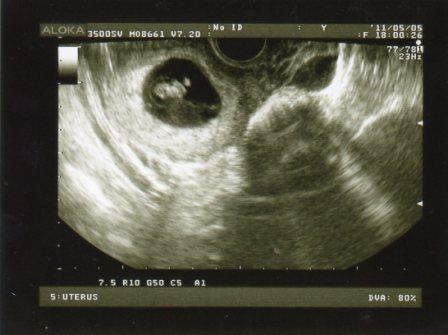

Voltam ma UH-n

! Petezsák: 20x17 mm, Minimanó: 2,3 mm és VAN SZÍVHANG

(azaz szívcső pulzálás -> így fogalmazott a dokibácsi). Elvileg 6. hetes terhes vagyok. Képem sajna nincs